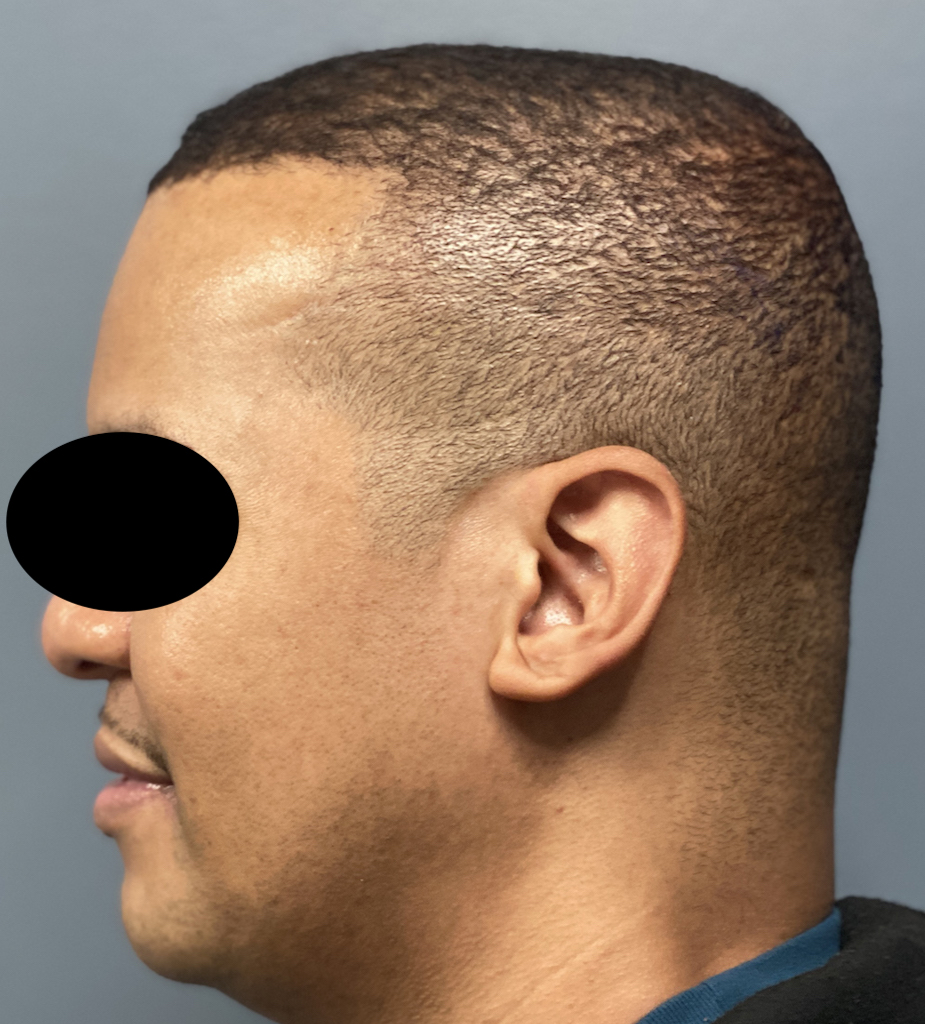

Desire for reshaping of an asymmetric flat back of the head in a shaved head male.

A combined back of the head reshaping procedure was done with a custom skull implant, sagittal ridge reduction and a right temporal muscle reduction.

Desire for reshaping of an asymmetric flat back of the head in a shaved head male.

A combined back of the head reshaping procedure was done with a custom skull implant, sagittal ridge reduction and a right temporal muscle reduction.